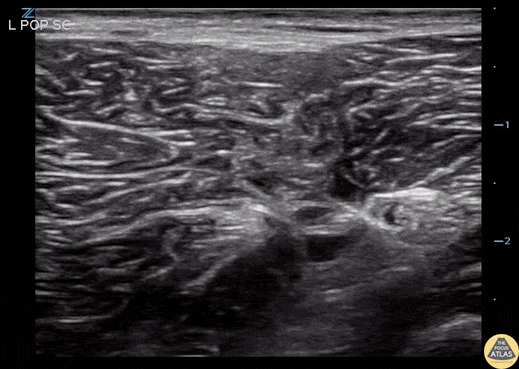

Nerve Block Gallery - Left Popliteal Sciatic Nerve Block

20 year old female with a history of IV drug use presents with a sizable calf abscess. She is admitted to the hospital for sepsis criteria and abscess drainage. She prefers no analgesia, therefore a popliteal sciatic nerve block is performed (demonstrated by injection of anesthetic adjacent to sciatic nerve) with resolution of her pain and successful incision and drainage. Contributors: John Bowling, DO (@BModeBowling); Bob Stenberg, MD (@POCUSaurusRex) Cleveland Clinic Akron General